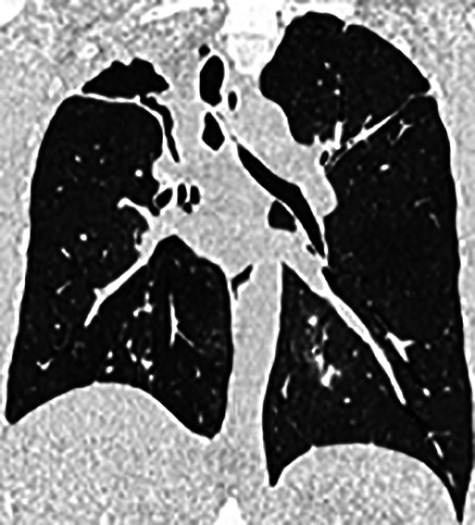

本研究证明了分枝杆菌或曲霉病慢性肺部感染患者靶向支气管内瓣膜腔的放射学可行性,并为方案制定提供了必要的数据。https://bit.ly/43STpPH。

This study demonstrates the radiological feasibility of targeting cavities with endobronchial valves in patients with mycobacterial or aspergillosis chronic lung infection and provides essential data for protocol development. https://bit.ly/43STpPH.